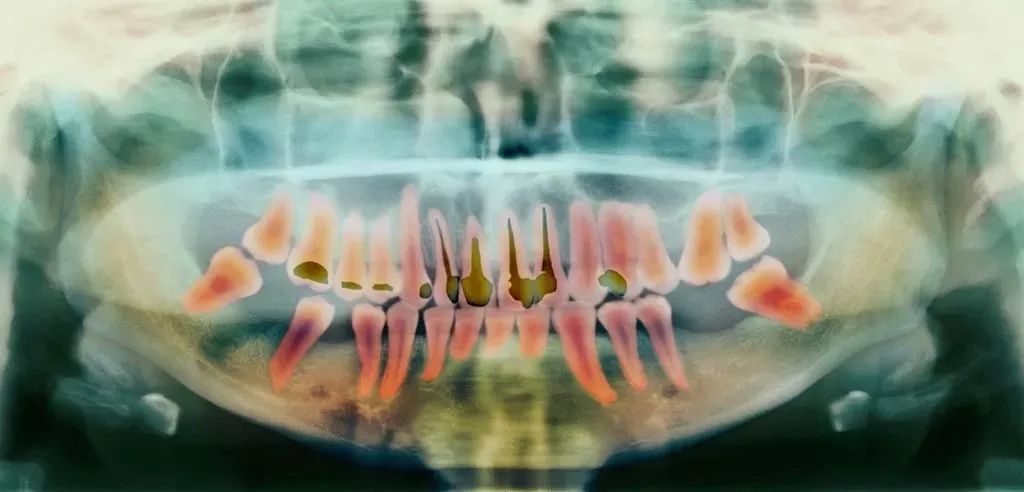

前牙根管需要治疗的牙根数量少,价格也就相对便宜;反之,后牙相较于前牙的价格会贵,双尖牙的根管治疗是最难的,因此,根管治疗的价格也是最贵的。

另外,除了根管治疗本身的费用外,还需要加上手术后保护牙齿的牙冠费用,而牙冠的价格,主要与材料有关。

前面就讲过了,当蛀牙才刚刚萌发的时候进行治疗,只需要简单补牙就可以解决了;但当蛀牙侵害到牙髓和神经,就不得不根管治疗了。

但是蛀牙初期发生的时候往往不会有任何感觉,如果你已经感觉到酸楚或者疼痛了,可能已经晚了,这个时候就不得不进行根管治疗,耗时耗力又费钱了。